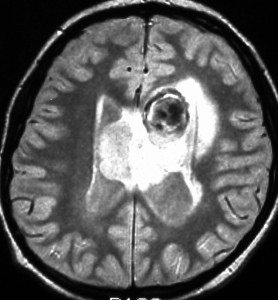

10歳の時に水頭症による頭痛と嘔吐で発症しました。結節性硬化症に合併したSEGAです。生検術,内視鏡手術,開頭術を受けて腫瘍を小さくして,その後にエベロリムスの投与を受けていました。これはエベロリムス投与後の画像です。この腫瘍にさらにエベロリムスの投与を続けるかという疑問があります。やめれば再燃することが多いからです。

結論として,これは完全摘出できるので摘出した方がいいです。なぜならそれでこの腫瘍は治癒するからです。右のFLAIR画像で見られるように発生部位となる尾状核のところでは一見,脳組織との境界が不明瞭にみえるのですが,腫瘍はある程度の硬さがあるので脳組織との区別をすることができて,完全摘出できるものです。